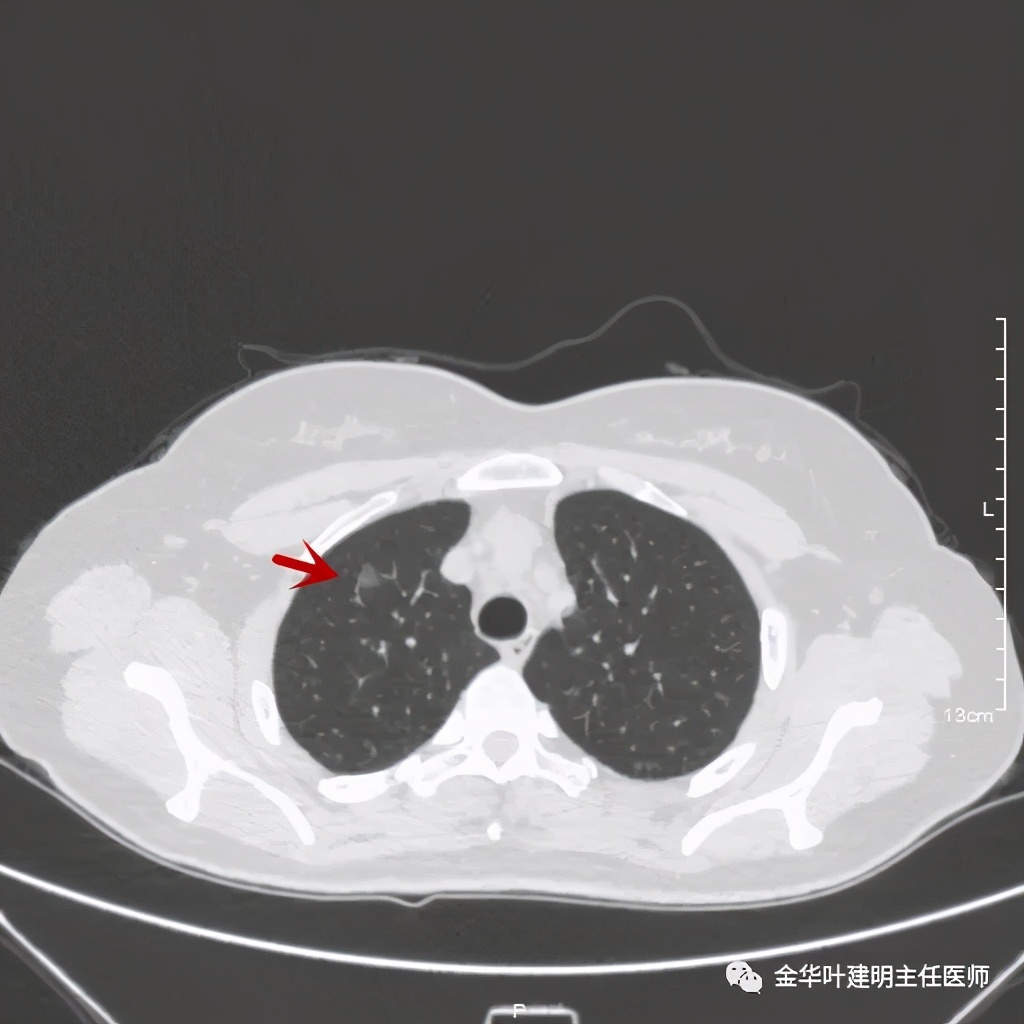

患者女性,50岁,检查发现右上肺结节已经近5年,我对比了其主病灶,密度略有增大,病灶看上去更清楚了,个人以为应该是微浸润性腺癌可能性较大,另有一次病灶,密度低,考虑腺瘤样不典型增生可能性大。我们先来看病灶:

上图示病灶1